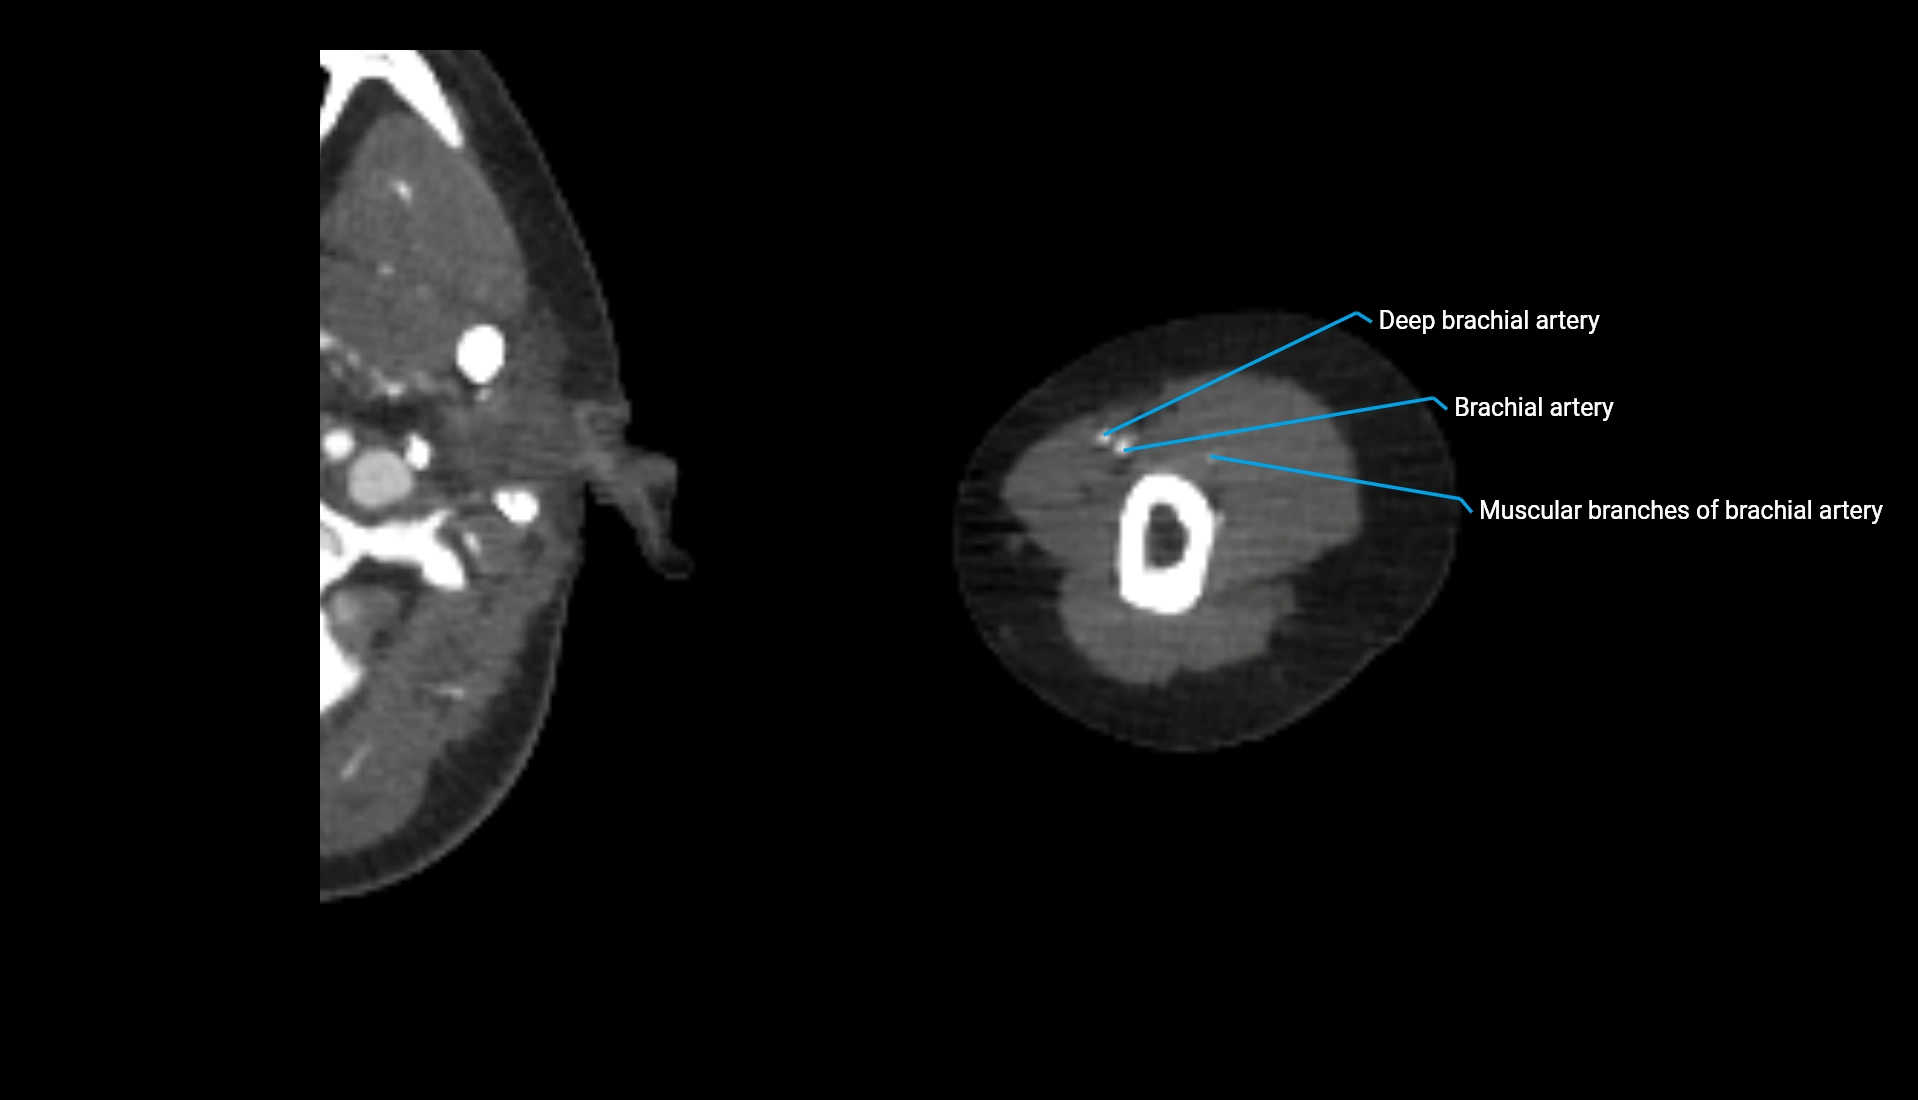

CT Appearance

Non-Contrast CT:

• Cortex: High-density, sharply defined

• Subchondral bone: Dense cancellous matrix

• Articular surface: Smooth concave contour articulating with the capitellum

• Excellent for evaluating bone integrity, alignment, and subtle fractures